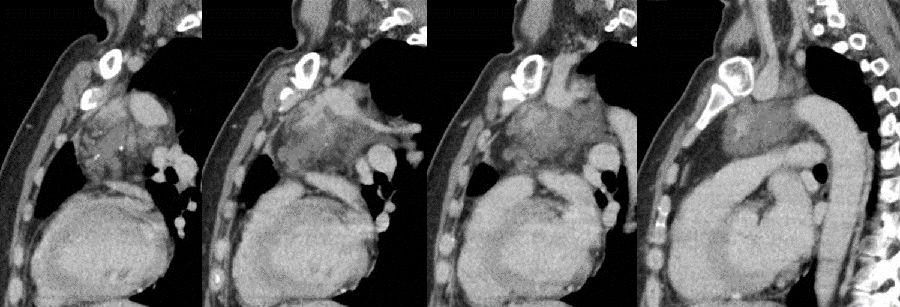

病例提供 伍建林教授(大连大学附属中山医院) 简要病史 患者,女,45岁 主诉:胸前区疼痛、胸闷3年,加重半月余。 现病史:3年前患者无明显诱因出现间断性胸前区疼痛、胸闷,伴后背部疼痛,运动后上述症状加重,无呼吸困难,无头晕、头痛,于当地医院行冠脉造影示:冠状动脉粥样硬化,具体治疗不详,出院后自服硝酸甘油,上诉症状可缓解。半月前,患者上诉症状加重,于当地医院行胸部CT检查发现:左前上纵隔肿物,并于我院门诊以“纵隔肿物”收入院进一步诊治。病来无咀嚼无力,无气短,无咯血,无关节疼痛,无进行性消瘦,无恶心、呕吐、低热盗汗等。 既往史:胸背部脂肪瘤术后8年;高血压病史4年,自服药物治疗效果良好;否认其他病史。 一般查体与专科查体无明显异常。 影像资料